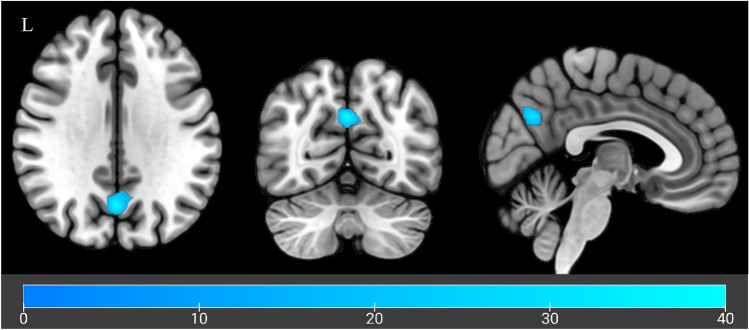

| Left | Precuneus | 191 | − 1 | − 67 | 32 | 0.038 |

When evaluating treatment effects (CBD vs placebo), CBD sessions were associated with significant hypoactivation for sessions in a cluster within the precuneus (MNI peak coordinates: − 1, − 67, 32, pFWE = 0.038; Fig. 2). This hypoactivation was evident across both control and alcohol cues, suggesting a non cue specific reduction within this cluster following CBD administration.

This is the first pharmaco-fMRI crossover design evaluating the neural effects of CBD on alcohol cue reactivity in non-treatment seeking participants with AUD. While there were no treatment effects seen for fMRI cue reactivity in the a priori defined regions (chiefly mesocorticolimbic) implicated in alcohol cue reactivity, whole brain analyses demonstrated CBD mediated reductions in cue reactivity relative to placebo, in a cluster of the precuneus during alcohol as well as control cue exposure blocks.

Non-cue-specific reduced activation observed following CBD administration suggests a general attenuation of brain activation in response to external cues. Previous studies have also observed that CBD modulated activation in the precuenous, but in tasks relating to verbal learning [ref. 66]. The precuneus is located between the sensorimotor cortices of the para-central lobule and the parieto-occipital cortex and is linked with subcortical and cortical structures. It is implicated as a hub serving the default mode network and the para-cingulate network, a subnetwork of the central executive network [ref. 67]. The precuneus is involved in episodic memory retrieval, visuospatial processing, and self-mental imagery [ref. 68], which are key processes in alcohol cue reactivity [ref. 69]. The precuneus has also been implicated in higher-order aspects of craving, including the subjective experience of craving [ref. 69]. Futhermore, previous cue reactivity studies have identified a relationship between severity of dependence and activation of the precuneus [ref. 69]. Therefore, given we did not observe any effects of CBD on subjective craving measures, it is plausible that greater treatment differences may emerge in treatment seeking samples and among participants with greater dependence severity.